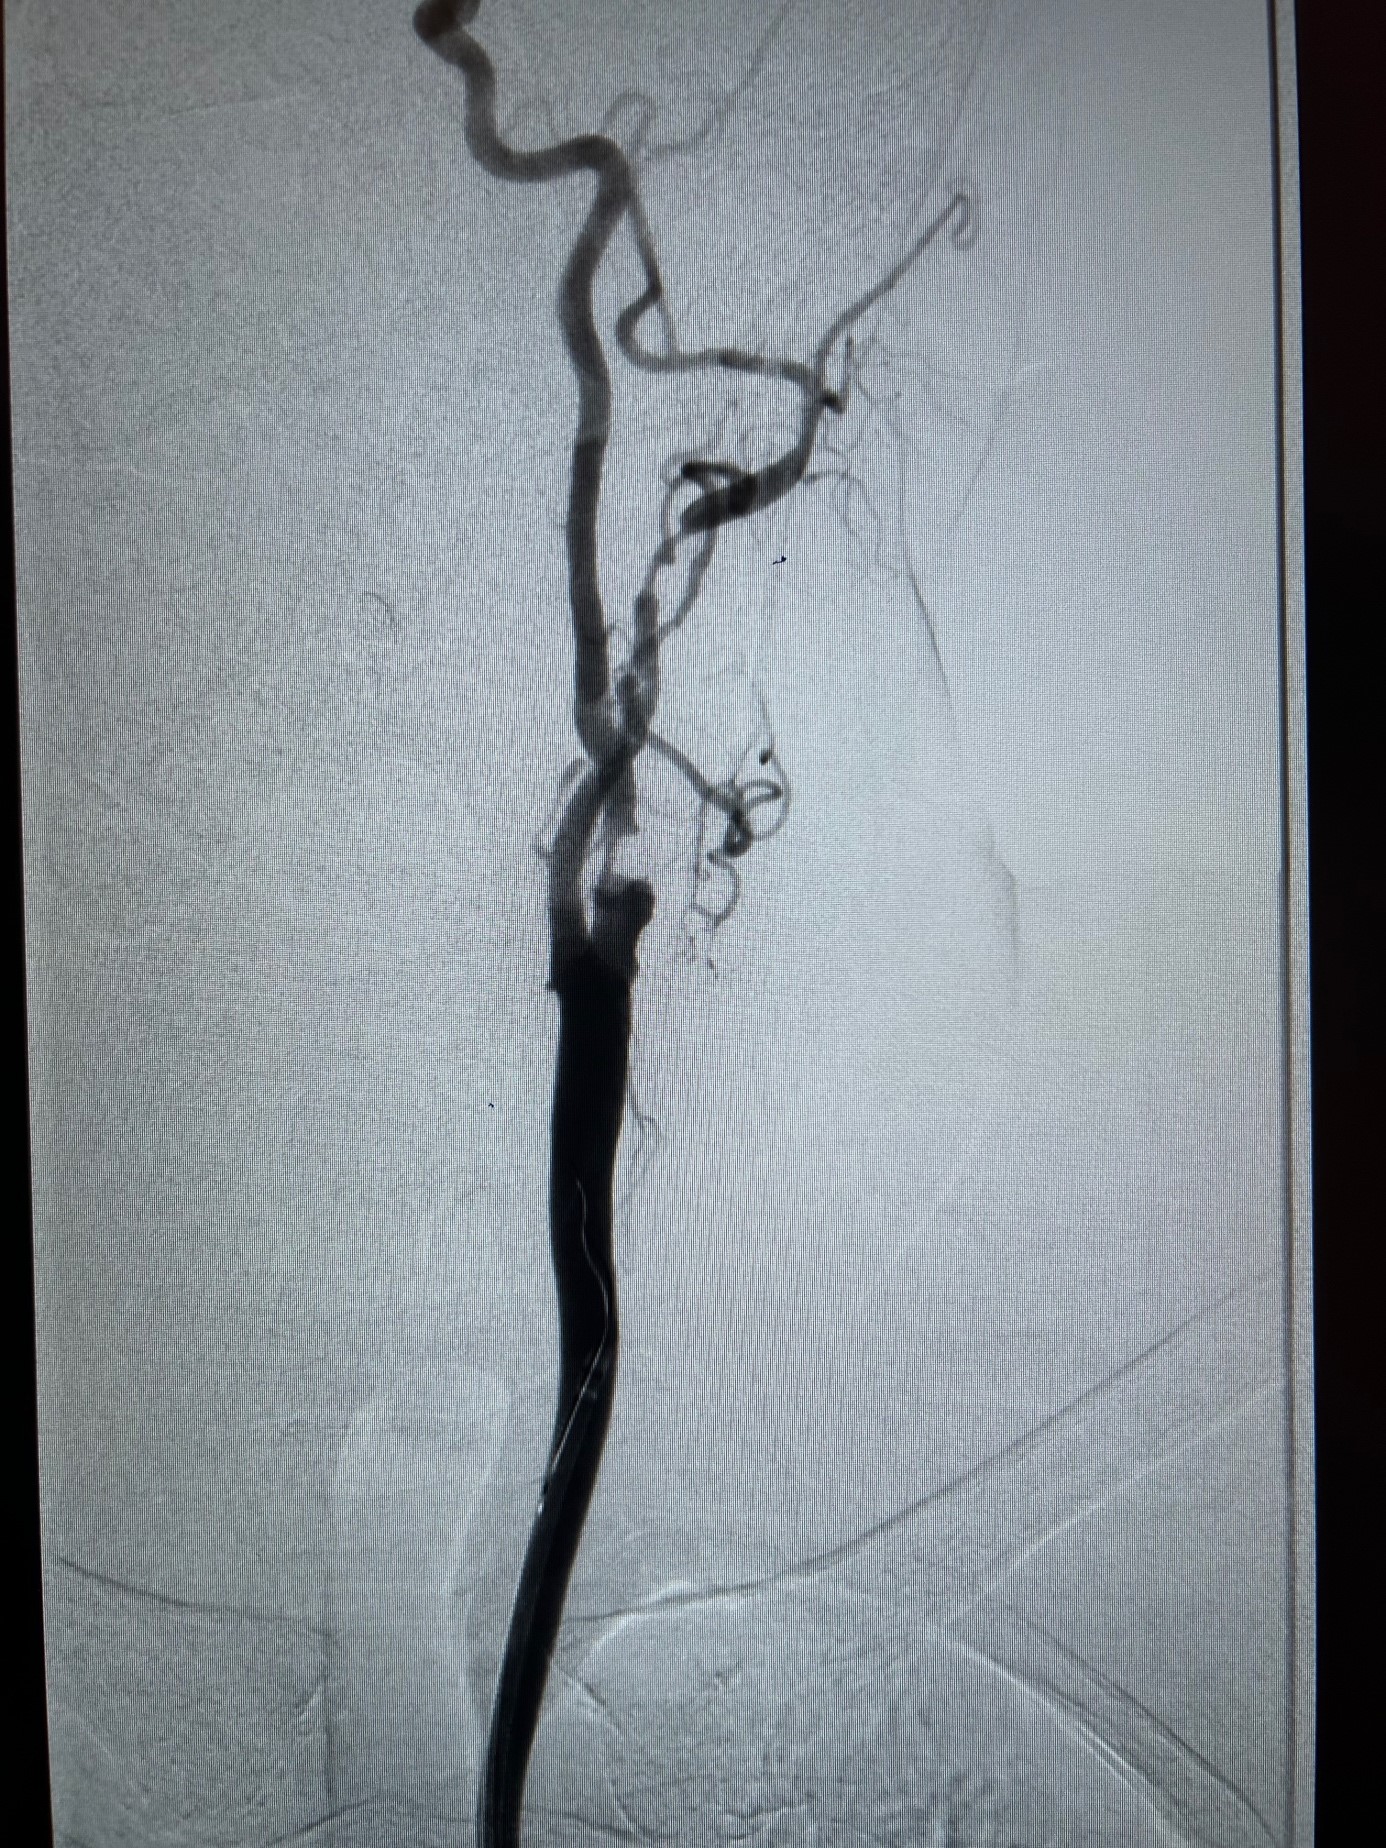

Lorsque la sténose est symptomatique ou lorsqu’une sténose asymptomatique est jugée à haut risque dans un cadre spécialisé, une revascularisation peut être discutée. Les deux grandes techniques sont l’endartériectomie carotidienne, qui consiste à enlever chirurgicalement la plaque, et l’angioplastie avec pose de stent carotidien, qui vise à traiter le rétrécissement par voie endovasculaire.

visualisation du flux sanguin et des zones rétrécies. Non invasif, il est l’examen de première intention à réaliser. Il permet de connaitre l’état de toutes les artères des membres inférieurs et de quantifier les degrés de sténose.

Angio-scanner ou IRM vasculaire

pour cartographier précisément les lésions avant chirurgie. L’angio Scanner des membres inférieurs, si la fonction rénale le permet (il faut injecter de l’iode pour réaliser un angio scanner) est l’examen de choix pour le chirurgien vasculaire;